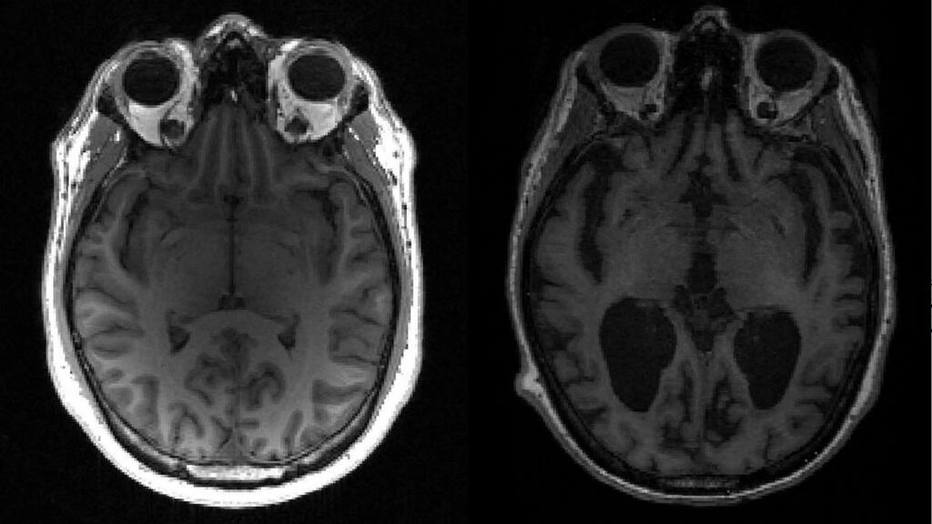

Um estudo da Academia Americana de Neurologia mostra que as pessoas em forma tem 33 por cento menos chance de desenvolver o Alzheimer.

O Alzheimer é o tipo mais comum de demência. É um distúrbio cerebral progressivo que, com o tempo, destrói a memória e as habilidades de pensamento, e interfere na capacidade de realizar tarefas diárias.